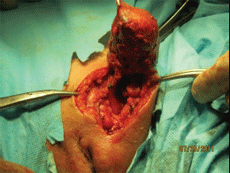

- Кожный разрез над пупартовой связкой с переходом на большую половую губу.

- Вскрытие пахового канала с последующим выделением круглой связки.

- Полное вылущивание кисты с капсулой из окружающих тканей с частичной резекцией круглой связки.

- Восстановление непрерывности круглой связки с последующей пластикой пахового канала.

Удаленный препарат представляет собой гладкостенную кисту овоидной формы, размерами 6,2x3,4см. На разрезе: множественные перегородки и полости, заполненные густой геморрагической жидкостью, похожей на “жидкий шоколад”. Больная выписана на третьи сутки в хорошем состоянии. При последующих посещениях какой-либо патологии в зоне оперативного вмешательства не выявлено.